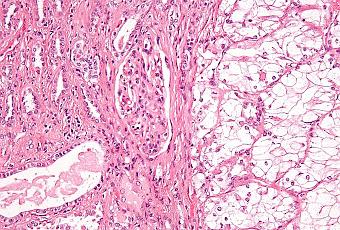

Micrographie d'un carcinome rénal, à droite de l'image; le rein non tumoral est à gauche de l'image.

Source iconographique et légendaire: https://www.wikiwand.com/fr/Cancer_du_rein